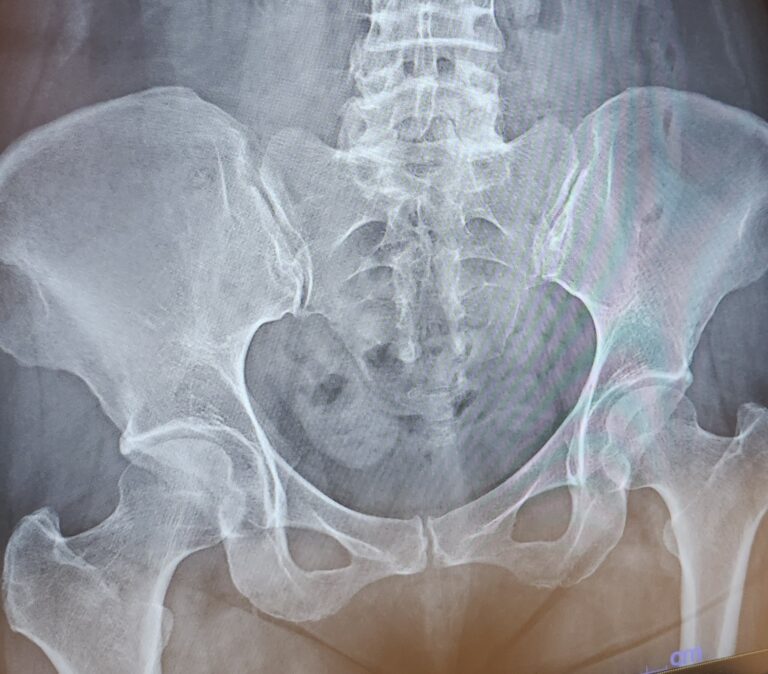

尾骨にヒビが入っていました

レントゲン撮影して見ていただくと、やはり残念ながら尾骨にヒビが入っていました 涙